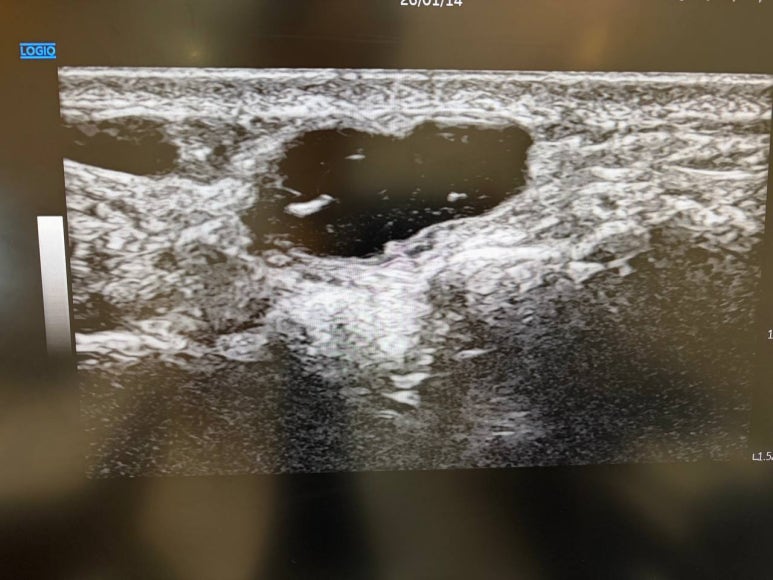

자, 먼저 손목을 한번 볼까요?

손등이나 손바닥 쪽에 콩알만 한

혹은 그보다 조금 더 큰 말랑말랑한

혹이 만겨지시나요?

이게 바로 '결절종(Ganglion)'입니다.

결절종은 손과 손목에 생기는

가장 흔한 연부 조직 종양입니다.

초음파로 바늘이 들어가는 길을

실시간으로 보면서

신경과 혈관을 피해 들어가기 때문에

통증은 최소화되고안전성은 극대화됩니다.